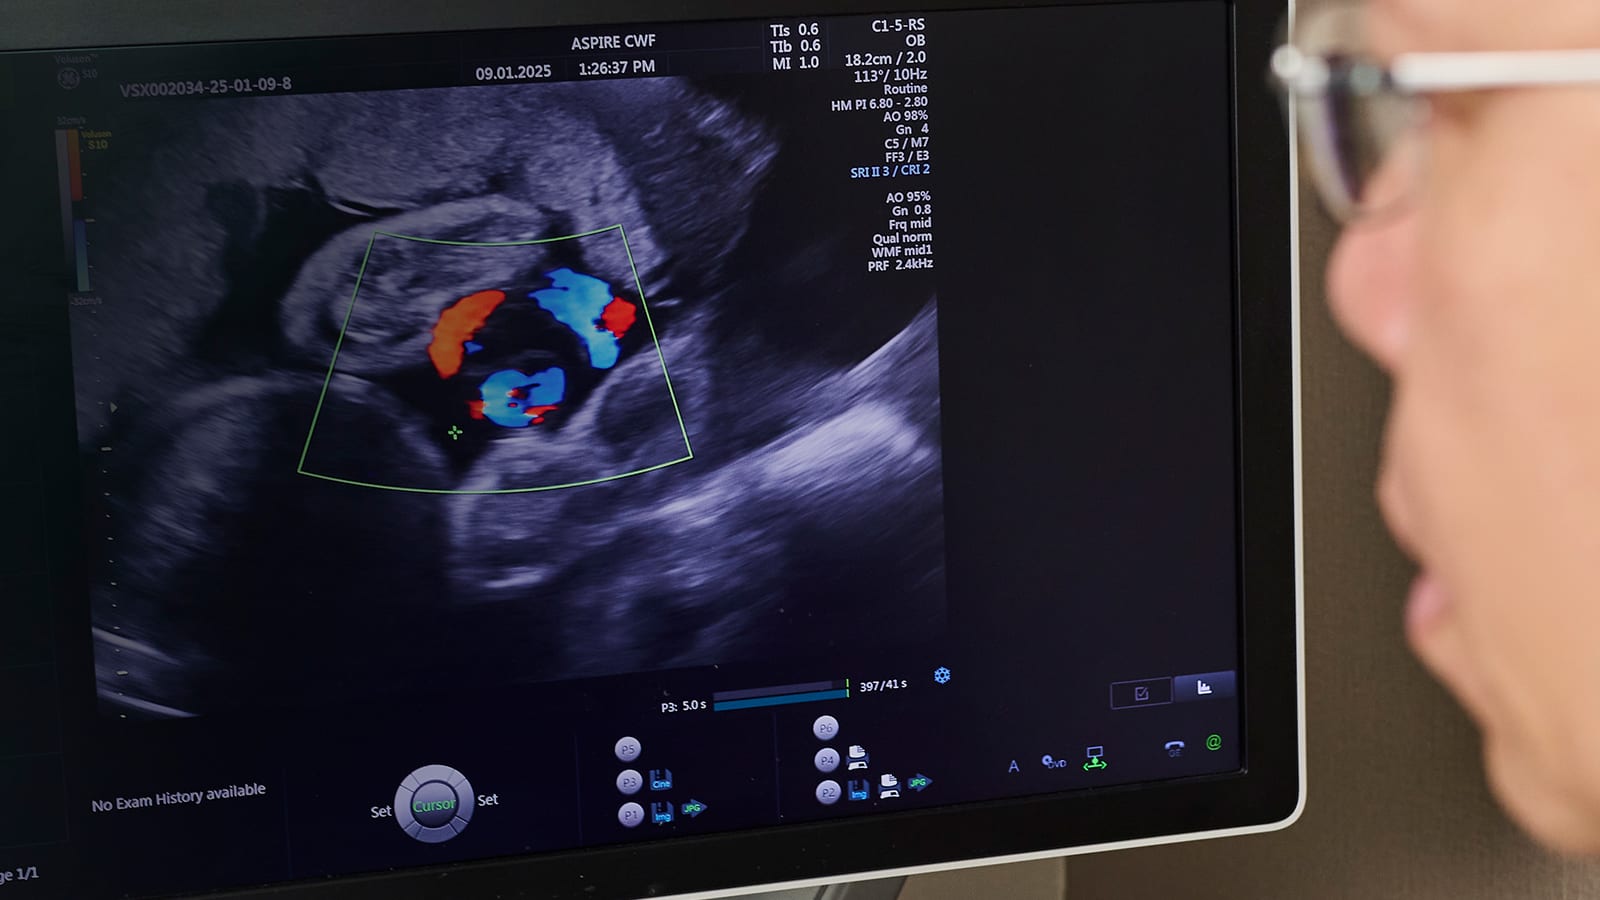

However, during a routine Pap smear, Ms Thiam decided to ask her gynaecologist, Dr Fong Yang of Aspire Centre for Women & Fertility, whether there was anything she could do to improve her chances of a successful pregnancy. “He did an ultrasound scan of my pelvis and discovered that the issue was that my womb had become enlarged,” Ms Thiam shared. “Dr Fong suggested that if I wanted to try again, I could undergo treatment to improve my chances of carrying a pregnancy to term.”

• Pelvic ultrasound imaging and X-ray to check for fallopian tube blockages